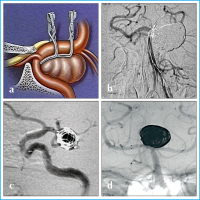

Filmsequenz zu Abbildung 7a-d: Chirurgie - Endovaskuläres Verfahren Ein wesentlicher Vorteil der chirurgischen Therapie gegenüber den endovaskulären Verfahren lag in der "rekonstruktiven Kapazität" des Aneurysmaclips, d. h. der Fähigkeit, komplexe Aneurysmahalskonfigurationen anatomisch korrekt unter Erhalt des aneurysmatragenden Gefäßes rekonstruieren zu können (a). Durch sogenannte "Neck-bridging devices" ist das in vielen Fällen auch durch endovaskuläre Techniken möglich geworden ("Balloon remodelling" [b], TriSpan Device [c], stentgestützte Coil-Embolisation [d]). |